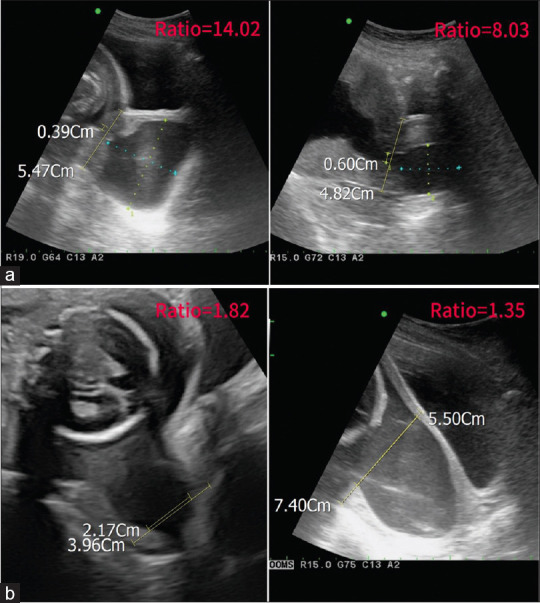

Cervical insufficiency poses risks for premature birth and neonatal outcomes. Preoperative sonography aids in the diagnosis and therapeutic considerations. Cervical cerclage is effective but carries risks. In our case series, 8 cases failed to complete emergent cerclage, leading to adverse outcomes. Analysis of preoperative images revealed thicker cervixes and cervical strictures may affect the surgical outcomes. Larger studies are needed to determine the reliable cutoff values. Preoperative assessment is crucial to inform treatment decisions.

宫颈功能不全对早产和新生儿结局构成风险。术前超声检查有助于诊断和治疗。宫颈环切术是有效的,但也有风险。在我们的病例系列中,有8例未能完成紧急循环,导致不良后果。术前图像分析显示宫颈较厚和宫颈狭窄可能影响手术结果。需要更大规模的研究来确定可靠的临界值。术前评估对决定治疗至关重要。